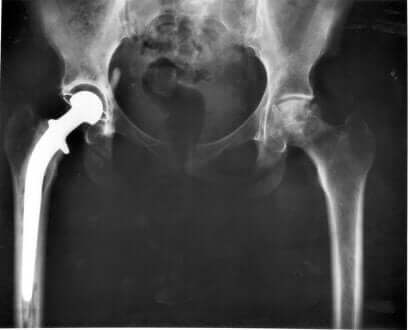

Il modo migliore per confermare la diagnosi di displasia dell’anca è portare l’animale dal veterinario per sottoporlo agli esami fisici pertinenti. La radiografia è in genere l’esame definitivo per confermare la presenza di displasia dell’anca nel cane.

In caso di intervento chirurgico, il veterinario sceglierà tra la sostituzione totale o parziale dell’anca.